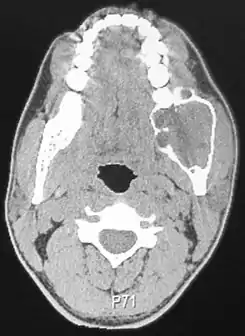

![]() Una Tomografía de un paciente afectado por un ameloblastoma | ||

El ameloblastoma se sospecha por los síntomas y estudios de imagen como radiografías, el diagnóstico de certeza precisa una biopsia y estudio histológico. Radiográficamente, aparece como una zona radiolúcida en el hueso, de tamaño y apariencia variables, en ocasiones es una lesión única, bien demarcada, otras veces se presenta como una «pompa de jabón» multiloculada. La reabsorción de las raíces de los dientes involucrados puede observarse en algunos casos, pero no es exclusiva del ameloblastoma. La enfermedad afecta con más frecuencia al cuerpo posterior y el ángulo de la mandíbula, pero puede presentarse en cualquier parte del maxilar inferior o superior. El ameloblastoma se asocia a menudo con muelas del juicio impactadas, una de las razones para que los odontólogos recomienden su extracción.